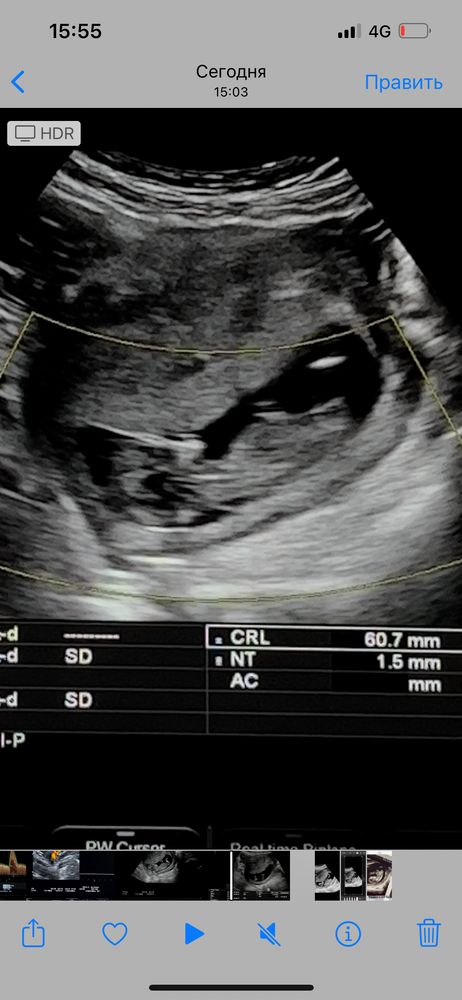

Всем привет 🤍 сегодня была на узи! 12,5недель, у меня есть 3 сына! ждём 4 малыша! Который 4,5 года к нам не приходил! сегодня снимала видео со скрининга, и думаю может можно что-то разглядеть?)) прилагаю скрины с видео , вид с боку и снизу 🤍 Благодарю за участия

Половой бугорок видно хорошо, он "торчит" практически параллельно телу, это же девчуля🥰

Похоже на девочку. Процентов на 80, как любят говорить врачи. Если на фото половой бугорок, то он параллельно позвоночнику